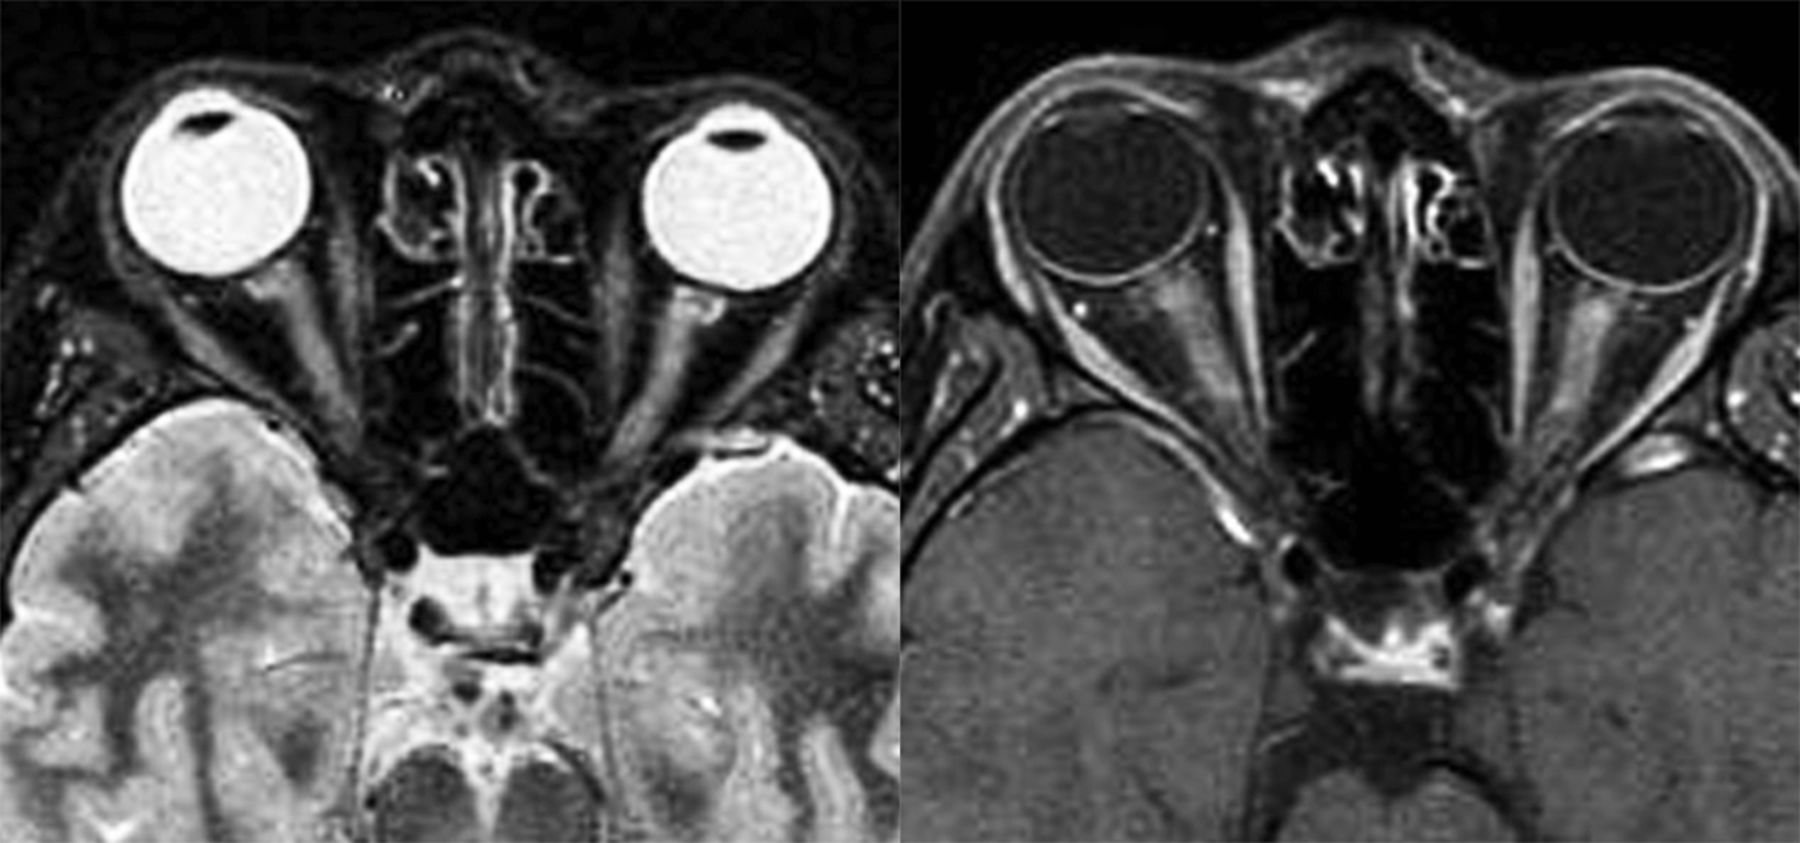

患者在攻击,我们发现18.8%(3/11)的MOG抗体群,AQP4抗体组的72.9%(72/96),和46.7%(14/30)的血清反应阴性的组视力< 20/200 (p= 0.0010)。一个病人(9.1%)为MOG抗体阳性,30.2%(29/96)的患者AQP4抗体阳性,13.3%(4/30)的血清反应阴性的患者没有光感知后的攻击。双边、同时袭击所有组中观察到,但这样的攻击更常见MOG患者抗体(见说明成像扫描图1)比AQP4抗体或人血清(72.7%(8/11)和24.0%(23/96)和36.7%(11/30),分别;p= 0.0035)。

图1

图1 双边视神经炎患者MOG抗体

轴向短TI反转恢复(搅拌),与钆t1加权磁共振视神经的28岁男子与两国同时视神经炎和髓少突细胞糖蛋白(MOG)抗体(效价1:4,096)显示与对比度增强双边搅拌hyperintense病变。